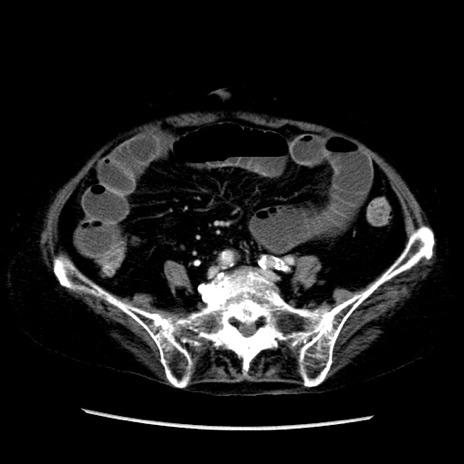

冠状断像

症例14(横断像)

【症例】 90歳代女性

【主訴】 腹痛・嘔吐

【現病歴】今朝から左側腹部痛を認めた。 経過観察していたが、嘔吐を認めたため来院。

【既往歴】 子宮癌術後

【身体所見】 意識清明、BP 127/54mmHg、P 98bpm Sp02 95%(RA)、BT 35.8°C、腹部平坦・軟腸ぜん動音聴取良好、右下腹部圧痛(+) 反跳痛なし

【データ】WBC 9800、CRP 0.46